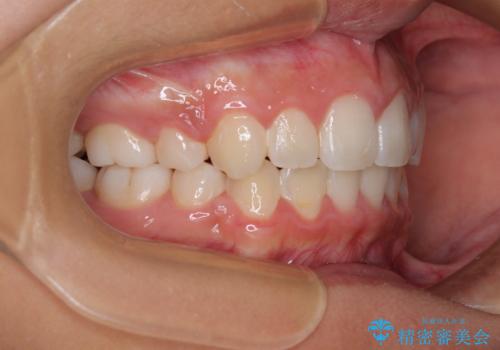

気がつくと唇があいてしまう ワイヤー装置での抜歯矯正

- 口元の突出感で口が閉じにくいとのことで来院された患者様です。

上下左右の第一小臼歯4本を抜歯し、ワイヤー装置での抜歯矯正を行うこととしました。

右側の咬み合わせは、上顎がやや前方位にある状態であったので、通常は補助装置を併用するのですが、高校生ということで補助装置なしで治療を行うこととしました。

口元の突出感が解消され、睡眠時の口呼吸が改善されました。